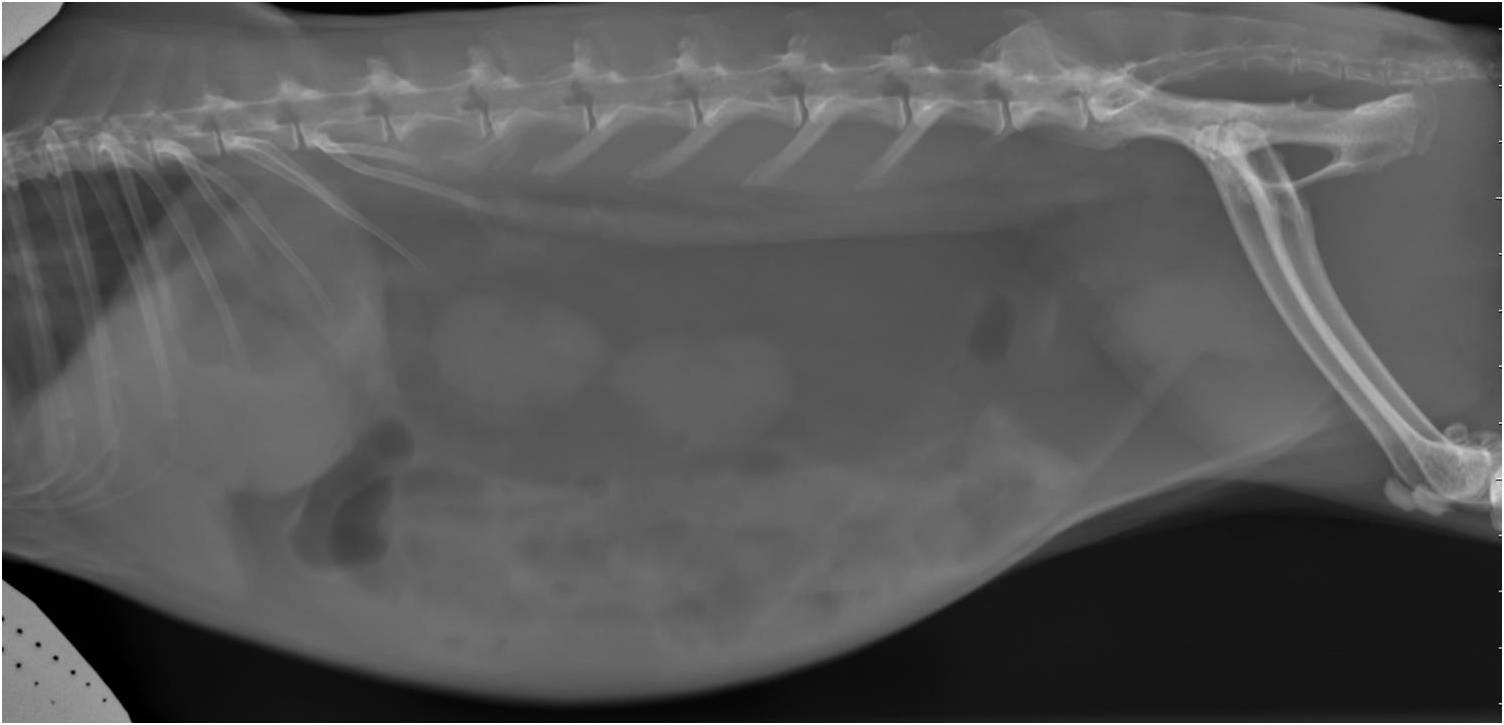

La sablose urinaire est courante chez le lapin ou le cobaye. Les causes sont généralement liées à un défaut d'hydratation, un excès de calcium alimentaire ou un défaut de mobilité (sédentarité). La présence de sable urinaire en grande quantité peut être irritant et provoquer des difficultés à uriner, de la malpropreté, des cystites ou du sang dans les urines.

Le diagnostic est relativement aisé par radiographie. Cependant, toutes les sabloses ne sont pas nécessairement pathologiques. Un bilan complet associant prise de sang et échographie est recommandé. Le traitement passe par une amélioration de l'hydratation et des rectifications alimentaires. Cette sablose peut prédisposer aux calculs vésicaux, urétéraux ou rénaux.

Calcul vésical

Les calculs urinaires dans la vessie sont courants chez le lapin et le cobaye et ils sont également observés plus rarement chez les chinchillas. Ils peuvent être particulièrement délétères et causer une douleur intense lors de l'émission des urines et la présence de sang dans les urines. En cas d'obstruction urinaire (impossibilité d'évacuation des urines), il s'agit d'une urgence vitale absolue pour le lapin et les rongeurs.

Le diagnostic se fait par radiographie mais une échographie et une prise de sang sont recommandés pour exclure la présence d'autres calculs au niveau des uretères et des reins et aussi pour vérifier l'absence d'insuffisance rénale. Le traitement est quasiment toujours chirurgical, certains cas particulier peuvent être traité par endoscopie ou par traitement médical.

Les lapines peuvent présenter de l'abattement et des pertes de sang (parfois spectaculaires). Elles présentent parfois des grossesses nerveuses (pseudogestation) associées au développement de la tumeur utérine. Le diagnostic se fait par échographie, d'une part pour confirmer la présence de la tumeur mais aussi pour faire un bilan d'extension et vérifier l'absence de métastases abdominales sur le foie ou la paroi abdominale. En cas de confirmation de tumeur, une radiographie thoracique doit systématiquement être proposée pour rechercher des métastases pulmonaires.